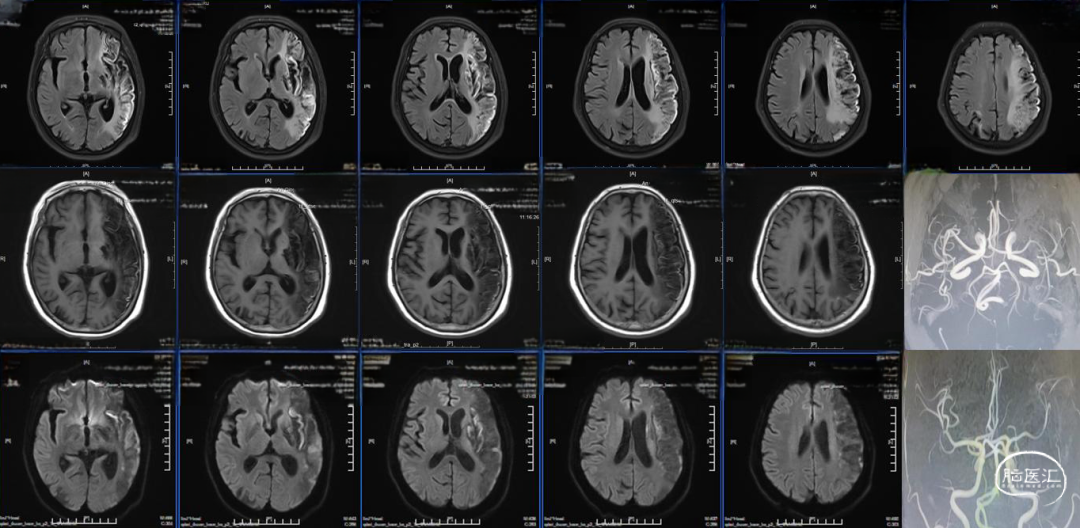

术后24小时复查CT,高灌注、轻肿胀,未见明显出血,轻度镇静至停用镇静,过程中可唤醒,自然复苏,呼吸机维持。

术后48小时复查CT,左半球大片低密度病灶、中线偏移,有主动睁眼、遵嘱动作,暂停呼吸机,延迟拔管,备去骨瓣。

术后96小时复查CT,左侧半球肿胀未继续进展,嗜睡,易唤醒、有睁眼、遵嘱动作,右侧肢体有自主动作,拔除气管插管。

术后第14天启动抗凝,术后第19天复查CT,术后第20天出院,NIHSS评分8分,mRs评分4分。

术后门诊随访,术后2月时mRS评分3分,术后4月时mRS评分2分,6月时随访mRS评分2分。